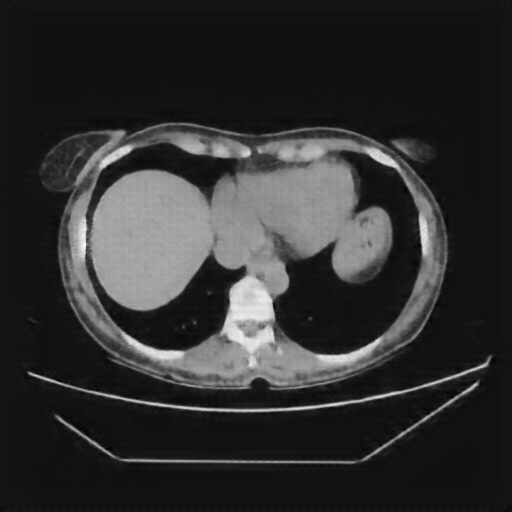

Original VENOUS CT scan

No window - Raw intensity values

Lung window (WL -600, WW 1500 β†’ Low βˆ’1350, High +150)

Mediastinum window (WL 40, WW 400 β†’ Low βˆ’160, High +240)